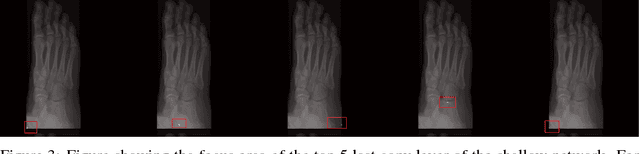

One of the main challenges for broad adoption of deep learning based models such as convolutional neural networks (CNN), is the lack of understanding of their decisions. In many applications, a simpler, less capable model that can be easily understood is favorable to a black-box model that has superior performance. In this paper, we present an approach for designing CNNs based on visualization of the internal activations of the model. We visualize the model's response through attentive response maps obtained using a fractional stride convolution technique and compare the results with known imaging landmarks from the medical literature. We show that sufficiently deep and capable models can be successfully trained to use the same medical landmarks a human expert would use. Our approach allows for communicating the model decision process well, but also offers insight towards detecting biases.